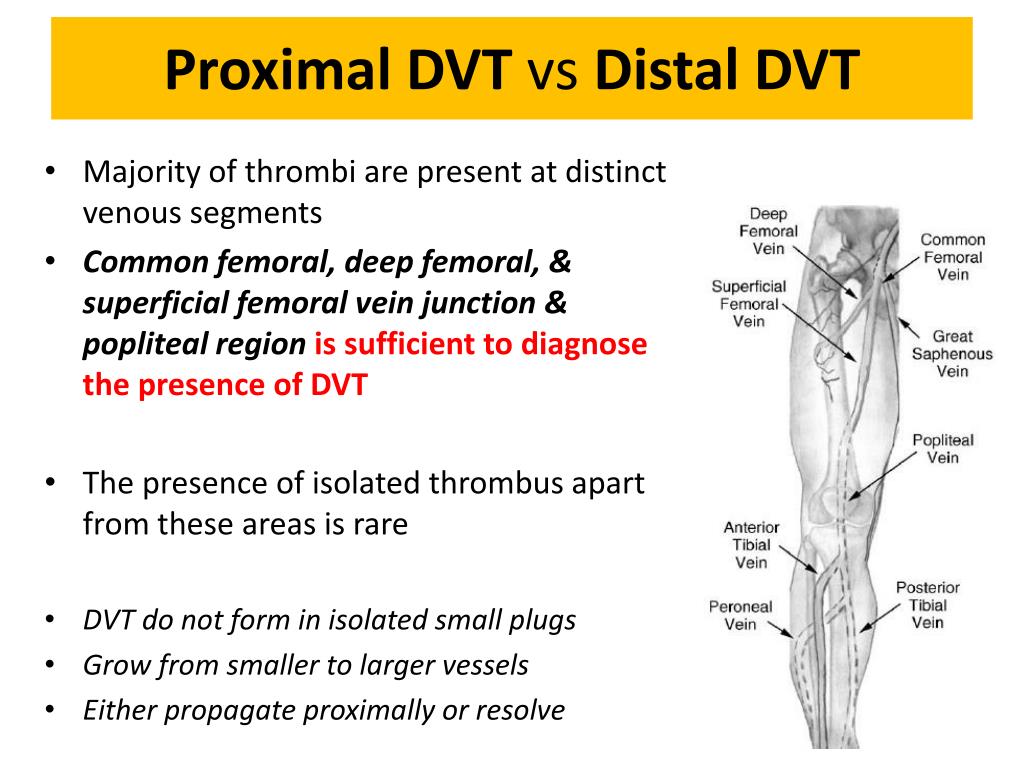

vte distal proximal dvt veins calf

vein thrombosis deep venous thromboembolism treatment prevention femoral common thrombus distal proximal knee ppt secondary powerpoint presentation